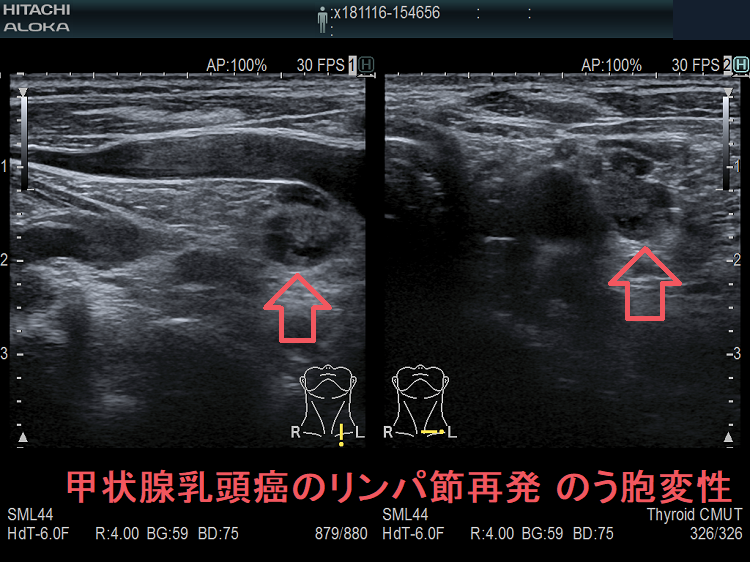

甲状腺乳頭癌鎖骨上窩リンパ節転移再発 のう胞変性(嚢胞変性)

甲状腺乳頭癌の左鎖骨上窩 リンパ節再発 のう胞変性 超音波(エコー)画像

甲状腺乳頭癌の左鎖骨上窩 リンパ節再発ですが、のう胞変性(嚢胞変性)をおこしているため、正常なリンパ節で無いのは一目でわかります。

甲状腺乳頭癌の左鎖骨上窩 リンパ節再発 のう胞変性 超音波(エコー)画像ドプラーモード

甲状腺乳頭癌の甲状腺乳頭癌の左鎖骨上窩 リンパ節再発 のう胞変性(嚢胞変性) 超音波(エコー)画像 ドプラーモード